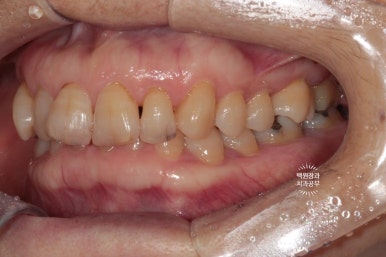

옆에서 보아도 너~무 잘 보이는 앞니 세로 금. 치아의 끝단에는 충치로 생각되는 어둑함이 자리잡고 있었고..

사진을 보시면 아시겠지만, 오른쪽 위 어금니 두개가 없으신 상태였습니다.

빼뚤빼뚤하기도 하면서, 금도 갖고 있었던 위 앞니들은 뒤에서 보면 이렇게 어둑하니.. 충치까지도 잘 보였습니다.